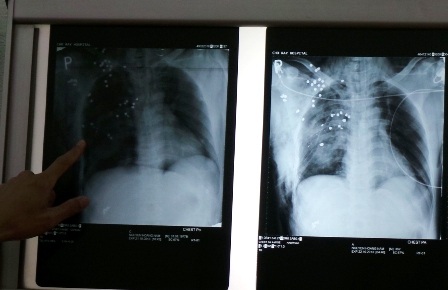

TS.BS Vũ Hữu Vĩnh, Trưởng khoa Ngoại lồng ngực cho biết: “Qua thăm khám lâm sàng ghi nhận, sườn phải của bệnh nhân bị một vết rách khoảng 5cm. Kết quả chụp phim X-quang cho thấy trong lồng ngực, phổi, bả vai bệnh nhân chi chít những mảnh đạn chì. Bị chùm đạn xuyên qua khiến một chiếc xương sườn bên phải của bệnh nhân dập nát, máu tràn vào màng phổi”.

Các bác sĩ đã nhanh chóng can thiệp gắp một phần các mảnh đạn có thể gây nguy hiểm đến tính mạng của người bệnh đồng thời cắt bỏ chiếc xương sườn bị dập nát, đặt ống dẫn lưu dịch từ màng phổi ra ngoài. Sau khi cấp cứu và chăm sóc tích cực, chiều 24/10 sức khỏe của bệnh nhân đang dần bình phục. Dự kiến, bệnh nhân sẽ phải trải qua nhiều cuộc mổ nữa để gắp những mảnh đạn li ti trong cơ thể ra ngoài.